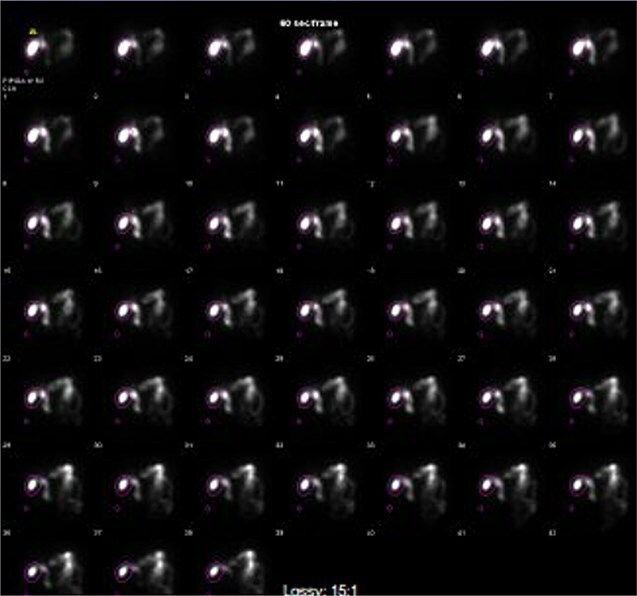

Computed tomography (CT) in the ER showed normal gastric bypass anatomy with moderate colonic stool burden. Negative for biliary pathology. Follow up ultrasound showed cholelithiasis without evidence of acute cholecystitis. A confirmatory HIDA showed normal filling of the gallbladder with rapid clearance into the small bowel and ejection fraction of 62% (Fig. 1).